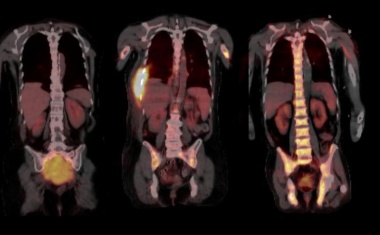

Ein neuer Ansatz für die Diagnose und Therapie von Lymphom-Erkrankungen steuert Chemokinrezeptoren (CXCR4), die während entzündlichen Prozessen und der Metastasierung von Tumoren hochreguliert werden, gezielt an.